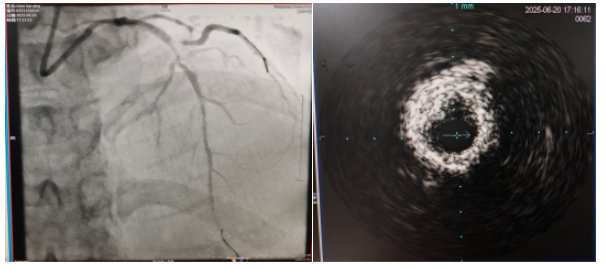

術(shù)中,趙慶禧主任醫(yī)師、雷剛副主任醫(yī)師運用IVUS血管內(nèi)超聲技術(shù)評估,發(fā)現(xiàn)患者前降支、對角支0.1.1型真性分叉病變,前降支近中段嚴重鈣化、成角并99%狹窄,對角支近段嚴重鈣化并99%狹窄,傳統(tǒng)冠狀動脈旋磨術(shù)容易引起冠狀動脈穿孔,決定采用沖擊波球囊技術(shù)即血管內(nèi)沖擊波鈣化碎裂術(shù)對患者嚴重鈣化的血管進行介入治療。通過球囊低壓擴張,向血管病變處發(fā)射非聚焦、低能量、脈沖式的沖擊波,對前降支及對角支進行了連續(xù)5個周期沖擊波脈沖治療,安全地碎裂淺、深層鈣化,原本看似堅不可摧的環(huán)形鈣化區(qū)逐漸顯現(xiàn)出了裂痕,多處關(guān)鍵位置發(fā)生了斷裂,充分預處理后于前降支近中段串聯(lián)植入支架3枚,對角支植入藥物球囊,術(shù)后造影見血管病變處狹窄完全消失,支架膨脹完全,貼壁良好,各項生命體征平穩(wěn),手術(shù)非常成功,患者返回心血管內(nèi)科病房繼續(xù)治療,并于4天后順利出院。